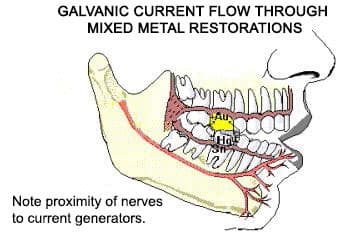

6. Mercury creates a battery effect in your mouth

It is known as oral galvanism. The high school science definition of a battery is having 2 dissimilar metals in the presence of an electrolyte. For you non-science people, just know that a mercury filling has at least 5 metals in it and you have in your saliva: calcium, sodium, chloride, potassium, and a whole bunch of other elements in the solution. So as you can see, you create a battery. You may have experienced this by touching a metal filling with a fork. You will get a decided metallic taste in your mouth. This is a great example of oral galvanism. This is present all the time if you have any metals present in your mouth. For those that have metal fillings, some type of malady (disease) may occur related to this phenomenon.